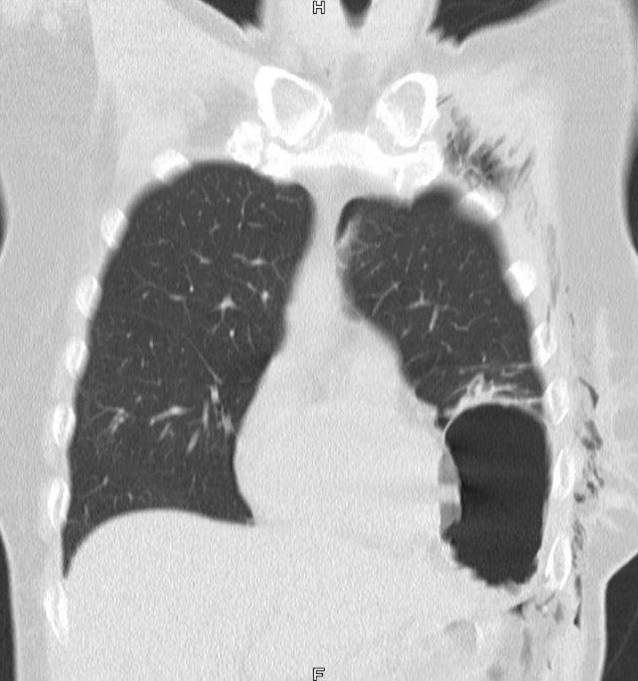

Über die Notaufnahme wurde eine 61-jährige, normgewichtige Patientin mit dem Rettungsdienst aufgrund multipler Schnitt- und Stichverletzungen vorgestellt. Neben potenziell lebensbedrohlichen Stichverletzungen zervikal, thorakal und auch abdominell mit Eröffnung der Bauchhöhle, zeigten sich im Bereich der inframammären Hautfalte links zwei 1,5 cm breite Stichverletzungen. Fremdanamnestisch hatte sich die Patientin die Verletzungen in autoaggressiver Intention im Status einer Wahnvorstellung bei bekannter psychiatrischer Erkrankung mit einem Messer selbst zugeführt. Bei kardioplumonal stabilem Zustand erfolgte die Diagnostik mittels einer Computertomographie (CT) des Thorax und des thorakoabdominellen Überganges. Durch die Radiologie erfolgte in Bezug auf die dargestellte Abb. 1 die Befundung eines gekammerten Hämatoseropneumothorax links. Zunächst wurde eine Magensonde angelegt. Laborchemisch ergaben sich keine wegweisenden Befunde. Die FAST(„focused assessment with sonography for trauma“)-Sonographie zeigte keine freie Flüssigkeit.

Abb. 1

Befund der Radiologie: gekammerter Hämatoseropneumothorax